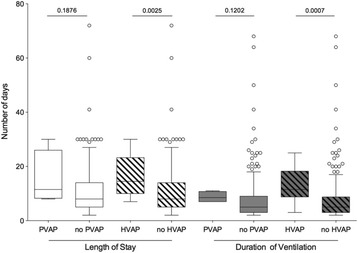

P163 - Effectiveness of fluid thoracic content measurement by bioimpedance guiding intravascular volume optimization in patients with septic shock

M. Aguilar Arzapalo, L. Barradas, V. Lopez, M. Cetina